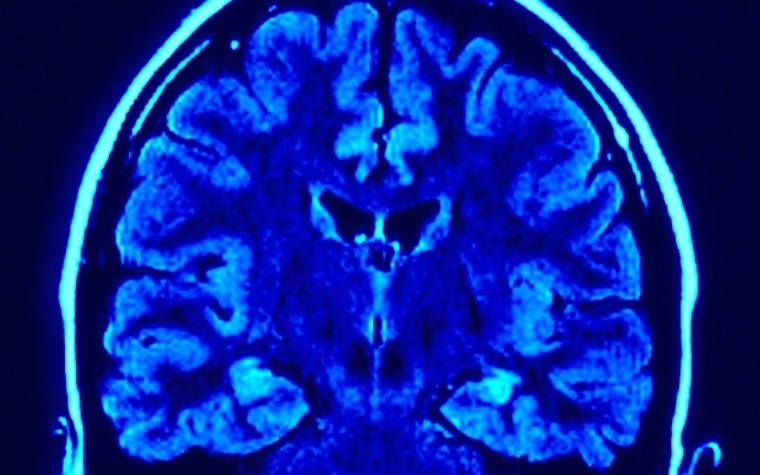

Rypma and fellow UT Dallas researcher Dr. Nicholas Hubbard coauthored a paper on their findings, which was published in The Journal of Neuroscience. They used functional magnetic resonance imaging (fMRI) and positron emission tomography (PET) imaging to study the brain activity of individuals, with more activity per unit of dopamine showing better facial recognition.